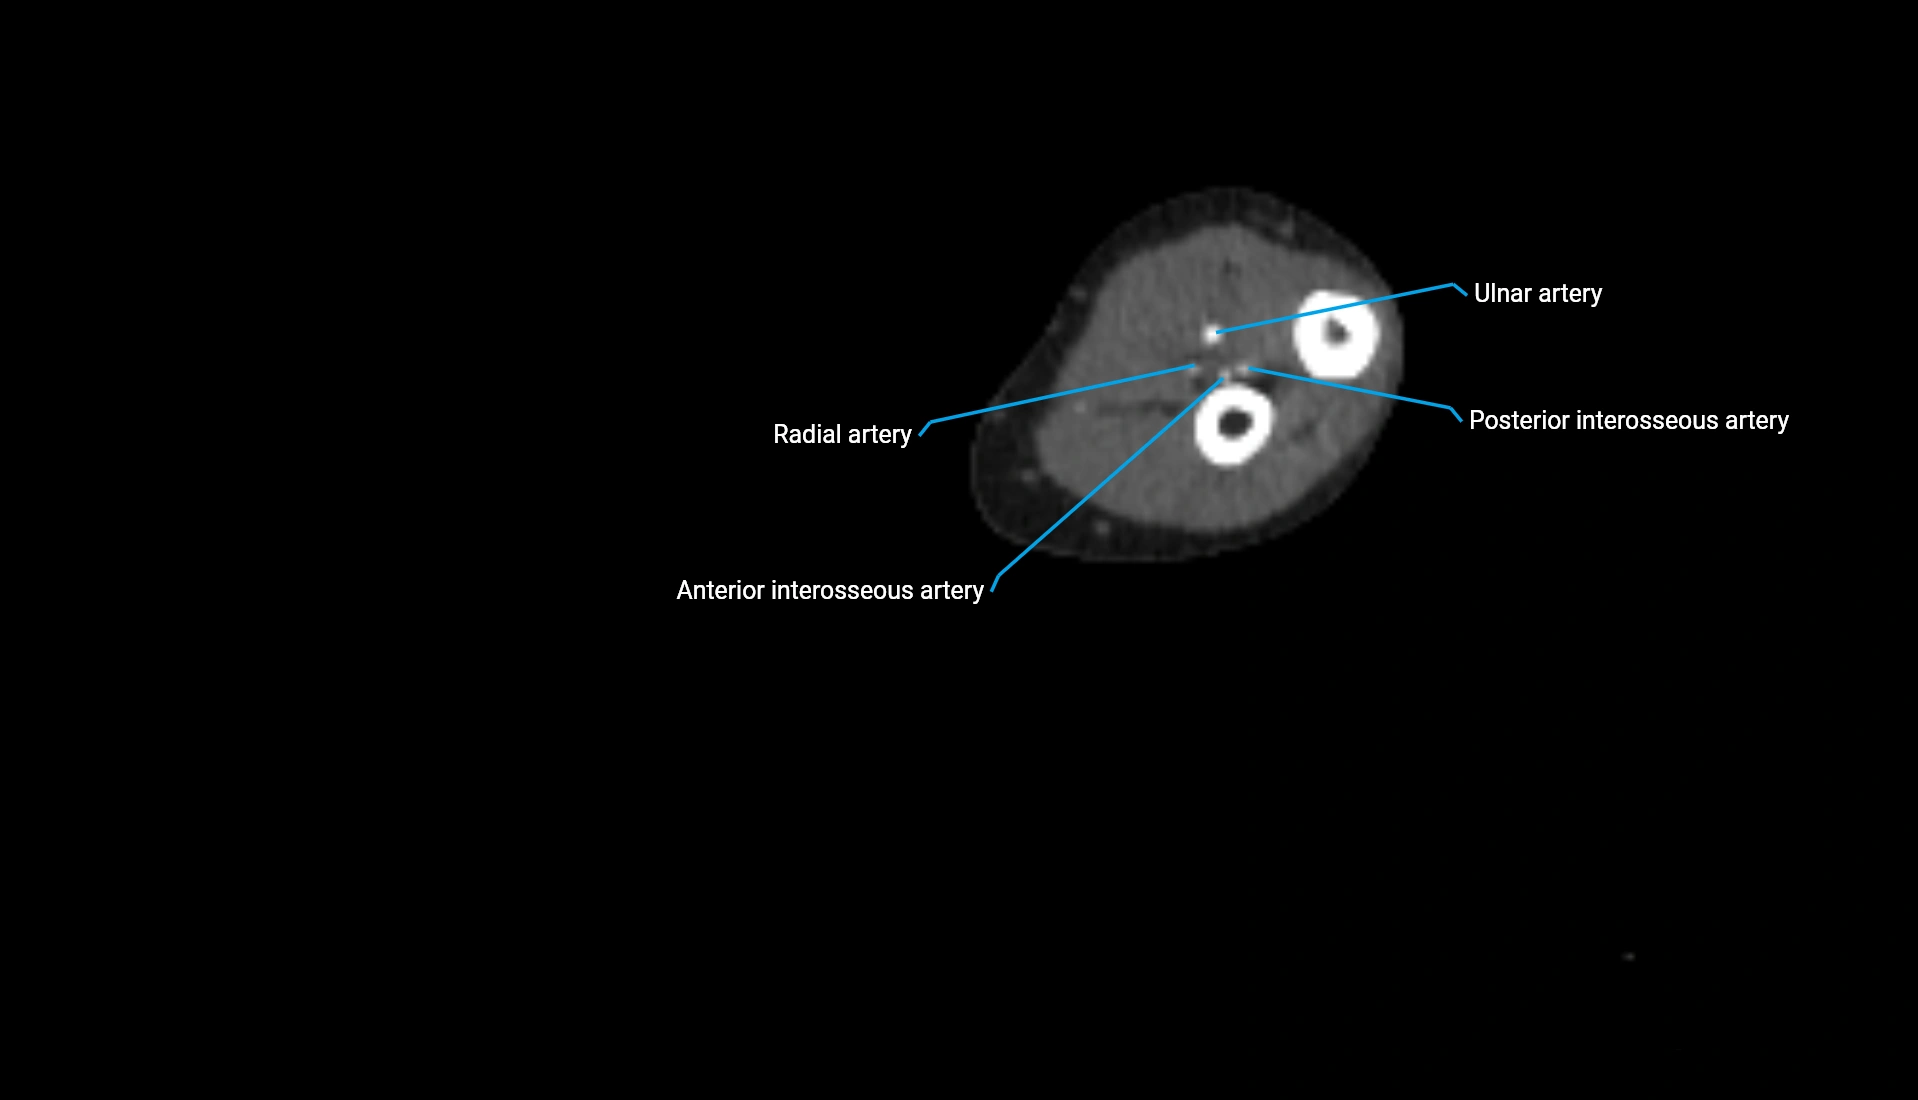

CT Appearance

Non-Contrast CT:

• Cortex: High-density, sharply defined

• Subchondral bone: Dense cancellous matrix

• Articular surface: Smooth concave contour articulating with the capitellum

• Excellent for evaluating bone integrity, alignment, and subtle fractures

Post-Contrast CT:

• Bone: No enhancement

• Joint capsule and synovium: Mild enhancement outlining the joint

• Improves contrast between soft tissues and bony margins

• Useful in detecting subtle joint abnormalities or postoperative changes